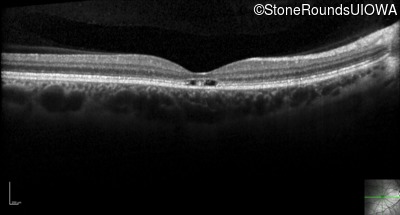

Optical Coherence Tomography - Left - 20/40

Exemplar / OCT Stack